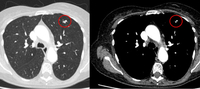

Tomografia computadorizada (TC) mostrando duas áreas (círculos vermelhos) de impactação mucoide dos brônquios subsegmentares do lobo superior esquerdo, resultando em aparência que mimetiza um nódulo

Do acervo de Dr. George Tsaknis, MD, PhD, FRCP (Londres), MRQA, MAcadMEd, PGCert; usado com permissão